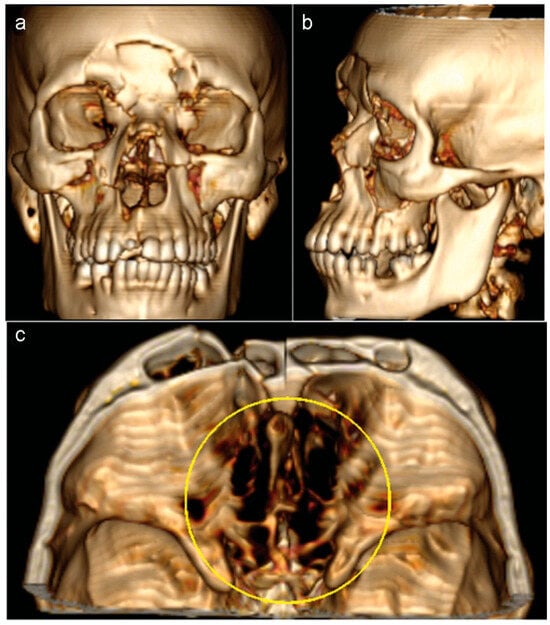

A 26-year-old male patient with a history of motorcycle accident presented with trauma in the naso-orbital-ethmoid region. The patient’s Glasgow coma scale score was 13/15 upon admission to the emergency room. Clinical examinations revealed CSF rhinorrhea, frontonasal sinking, and anosmia (Figure 1a). Computed tomography (CT) demonstrated multiple facial fractures, skull base defect in the cribriform plate region, and fractures of the posterior wall of the frontal sinus (Figure 1b–d and Figure 2a–c).

Figure 1. (a) A 26-year-old male patient with CSF rhinorrhea, frontonasal sinking caused by a motorcycle accident. (bd) Computed tomo-graphic scans showed a facial fractures, skull base defect in the cribriform plate region.

Figure 2. (a,b) Three-dimensional volume rendering images showing the forehead deformity and retrusion. (c) The size of the skull base defect.